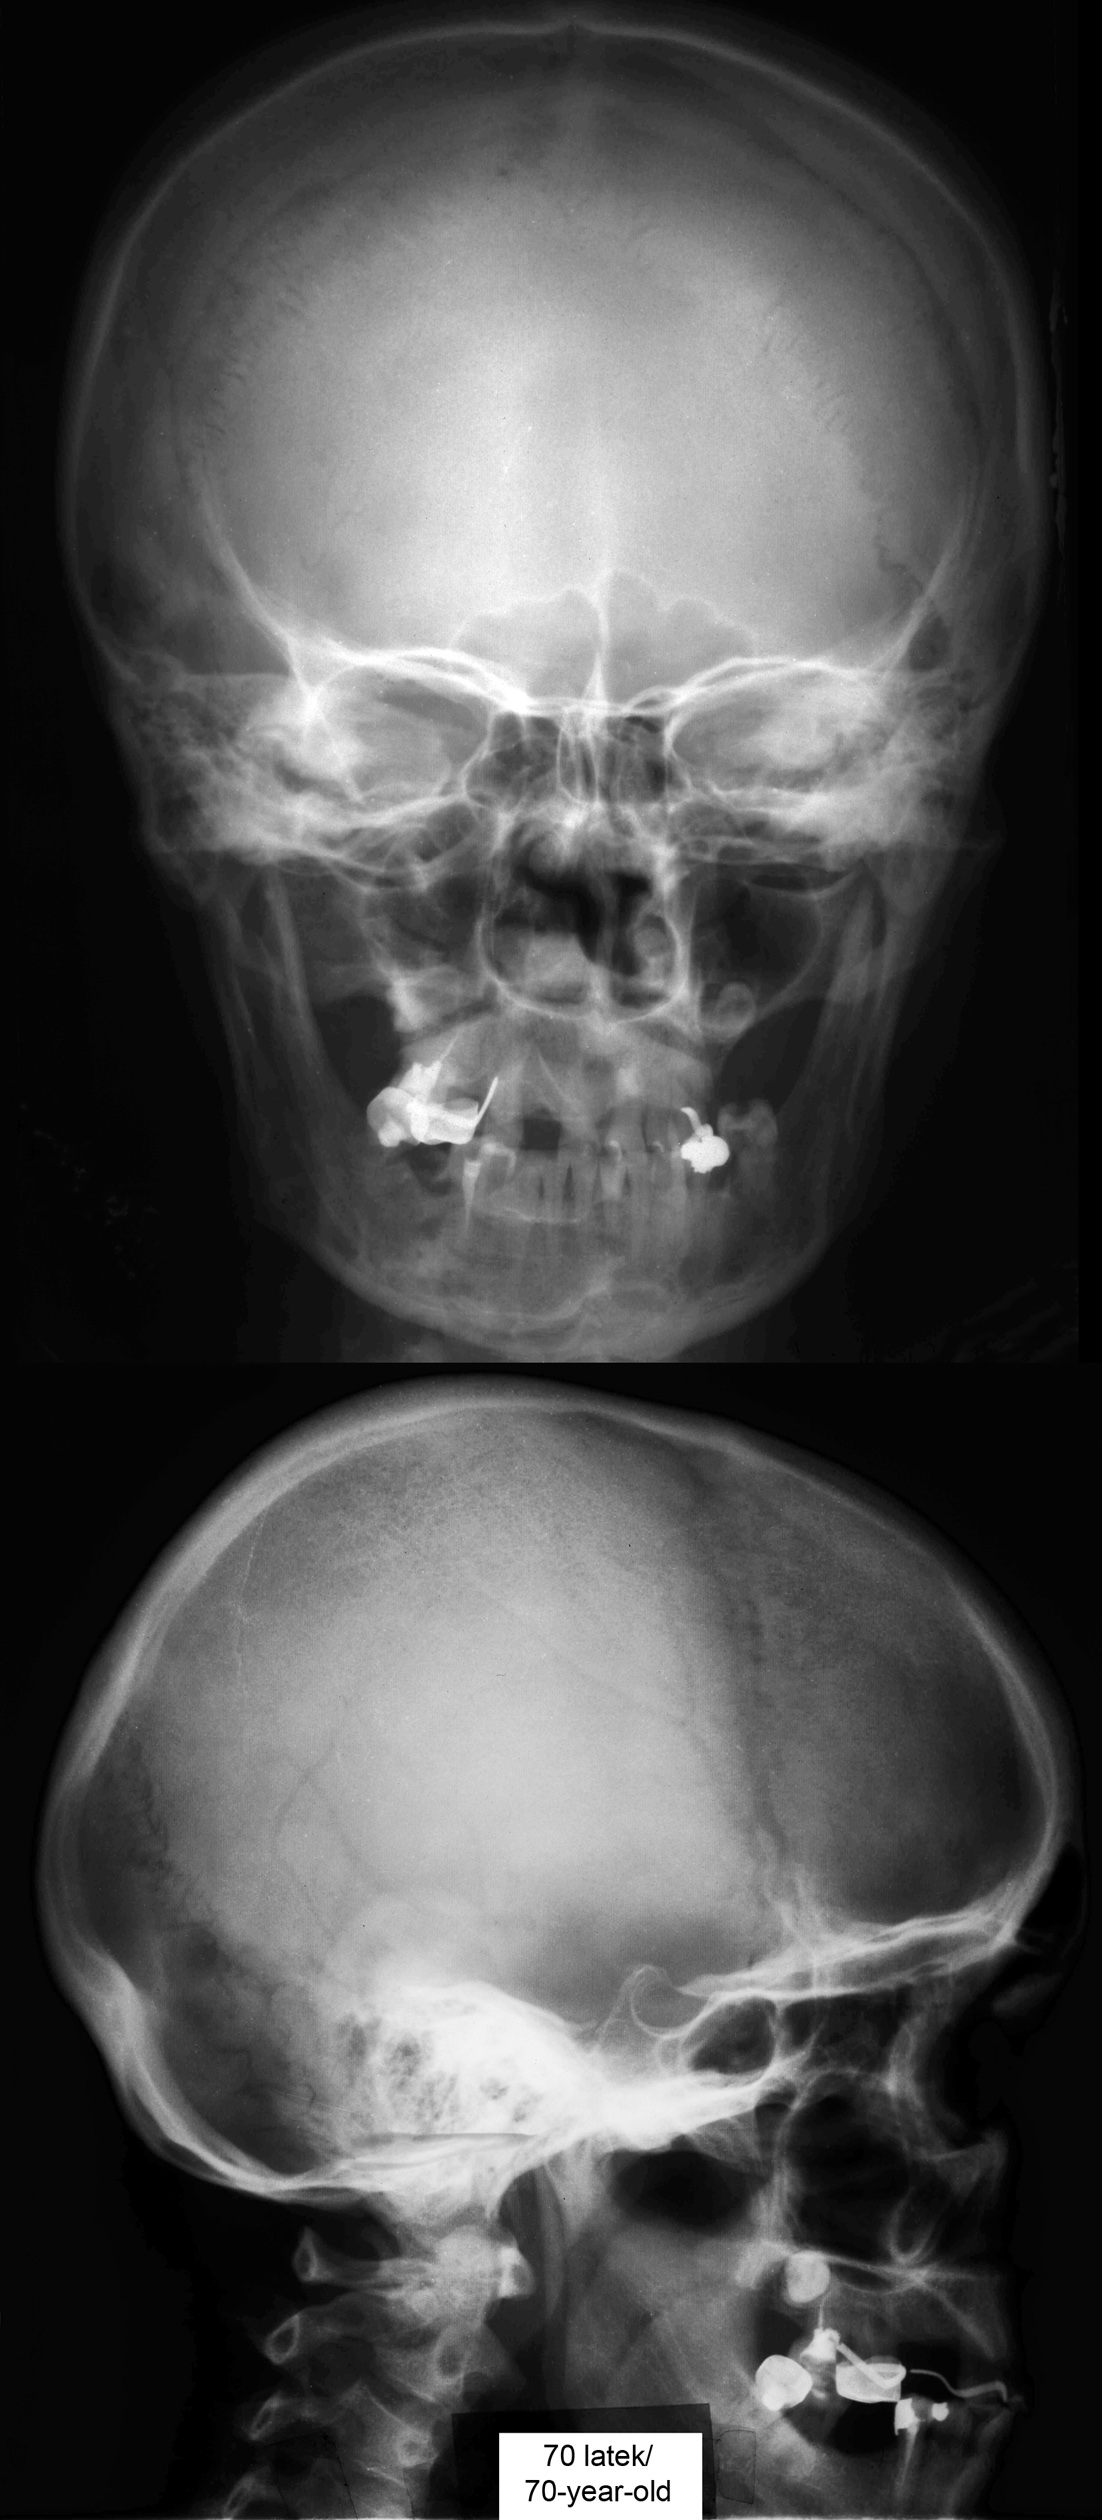

Radiografia / Radiography

RTG głowy 70-latka.